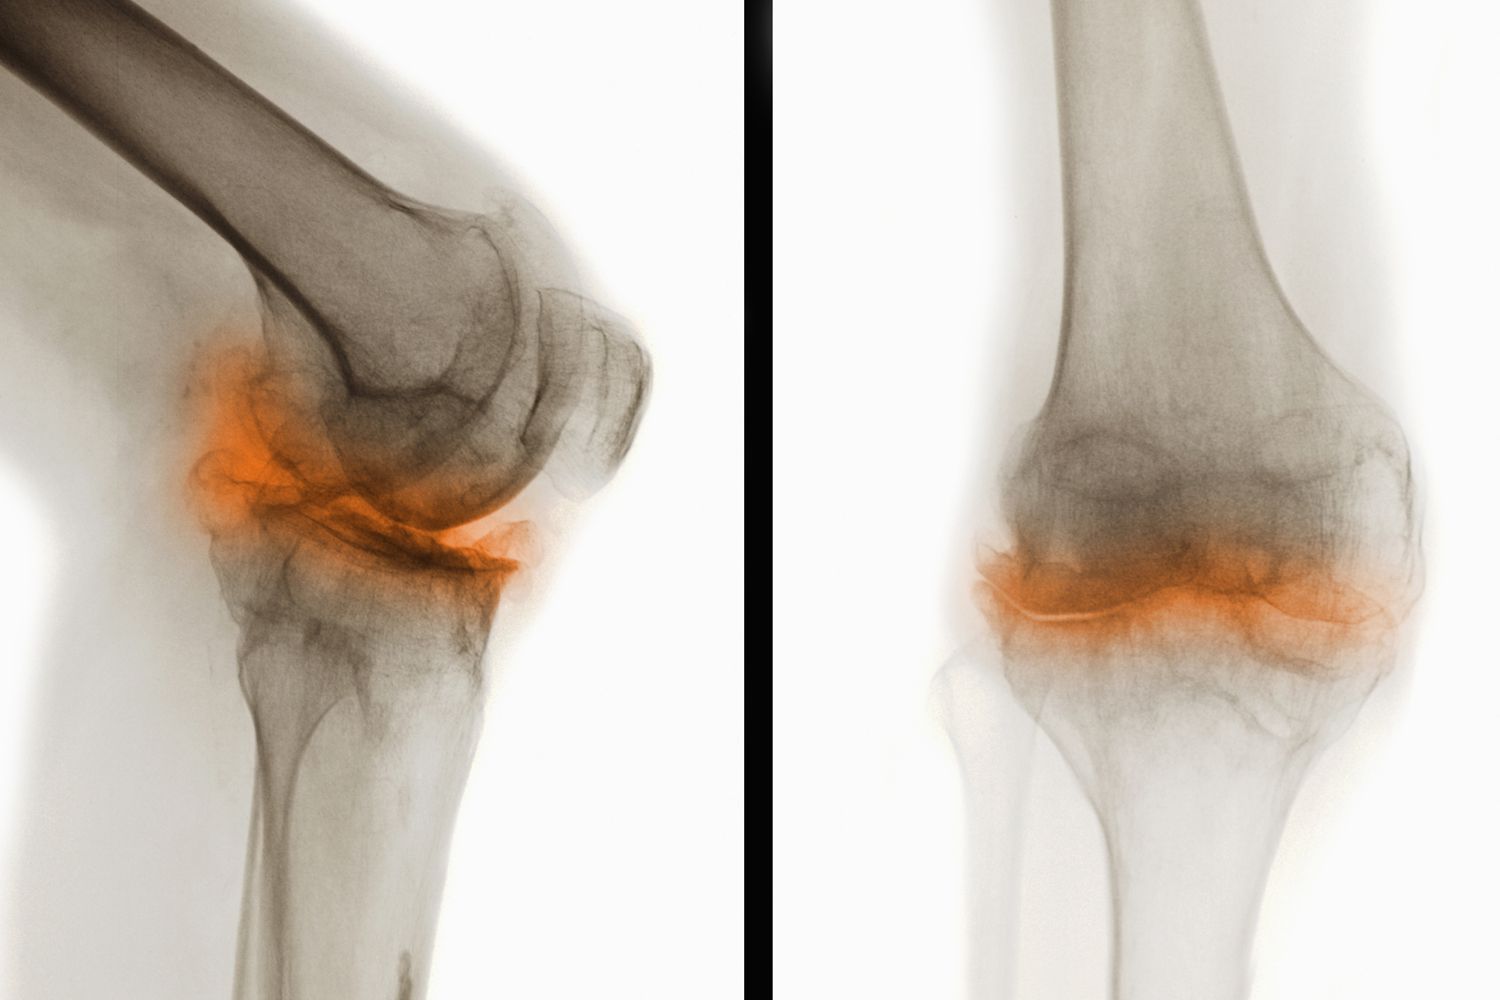

骨關(guān)節(jié)炎(Osteoarthritis,簡稱OA)是一種常見的慢性退行性關(guān)節(jié)疾病,主要表現(xiàn)為關(guān)節(jié)軟骨的退化和破壞,導(dǎo)致關(guān)節(jié)疼痛、僵硬和功能障礙。這種疾病通常發(fā)生在中老年人群中,尤其是負(fù)重較大的膝關(guān)節(jié)、髖關(guān)節(jié)、脊柱及遠(yuǎn)側(cè)指間關(guān)節(jié)等部位。

干細(xì)胞治療骨關(guān)節(jié)炎是一種新興且具有前景的治療方法。骨關(guān)節(jié)炎是一種常見的退行性關(guān)節(jié)疾病,主要表現(xiàn)為關(guān)節(jié)軟骨退化和骨質(zhì)增生,導(dǎo)致疼痛、僵硬和活動(dòng)受限等癥狀。干細(xì)胞治療通過利用干細(xì)胞的自我更新、多向分化和免疫調(diào)節(jié)能力,為骨關(guān)節(jié)炎患者帶來了新的希望。這也讓干細(xì)胞治療骨關(guān)節(jié)炎成為了研究的熱點(diǎn)。